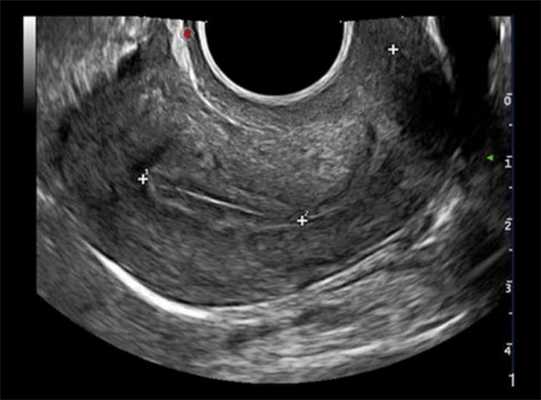

УЗИ шейки матки в норме

УЗИ шейки матки

Ультразвуковое исследование шейки матки - это важная диагностическая процедура, которую рекомендуют осуществлять как минимум один раз в год. С каждым годом заболевания матки и яичников молодеют. По этой причине гинекологи и акушеры рекомендуют заботиться о женском здоровье, начиная уже с 18 лет.

Норма шейки матки на УЗИ

УЗИ обычно делает сам врач-гинеколог, он же проводит расшифровку и интерпретацию. Если у пациентки не обнаружено патологических процессов, показатели варьируются в следующих пределах: длина шейки матки должна составлять не менее 35 и не более 45 миллиметров, размер маточного зева - не более 5 миллиметров, должна наблюдаться свободная проходимость цервикального канала. Структура эпителиального покрова должна быть равномерной, без изменений.